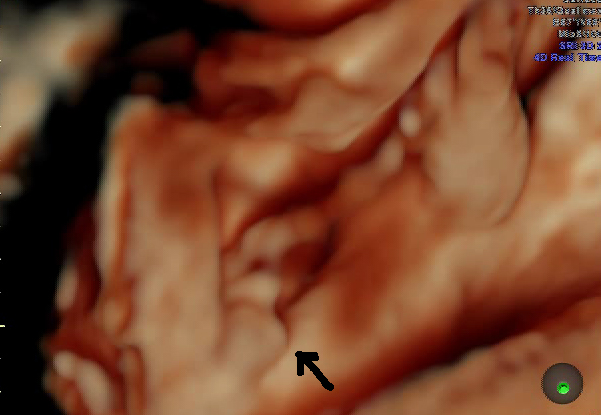

знакомая картинка)))))а на сроке 32 недель там ваще таакооое богатство)))

угу.у меня так что старший что младший.ну четко видно.перепутать нереально

Кайф!.. У нас тоже почти такой же снимок с писюном ;))

мужики!